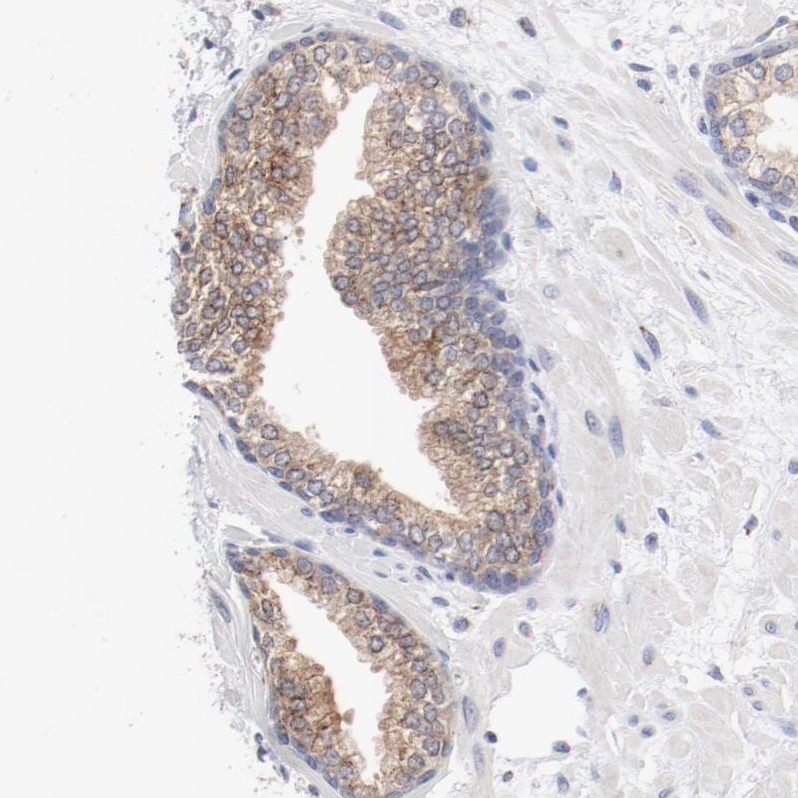

Immunohistochemistry analysis in human fallopian tube and lymph node tissues using HPA003543 antibody. Corresponding AK7 RNA-seq data are presented for the same tissues.